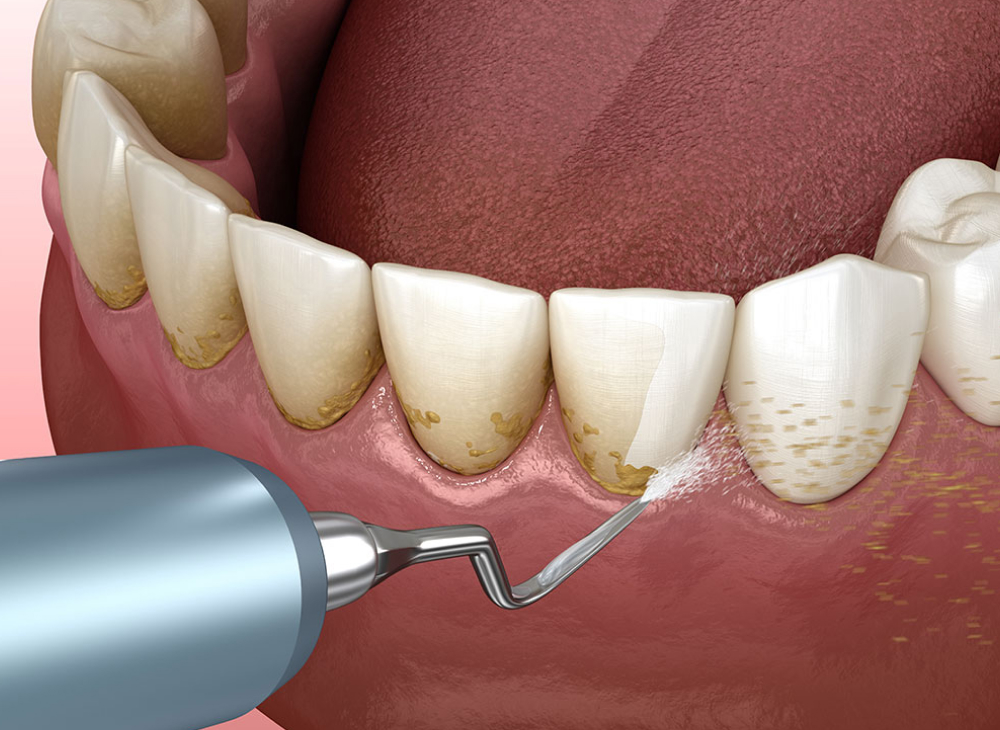

歯石除去

プラーク(歯垢)が石灰化して硬くなった歯石を、スケーラーという器具で取り除きます。歯石を除去することで歯周病の予防にもつながります。